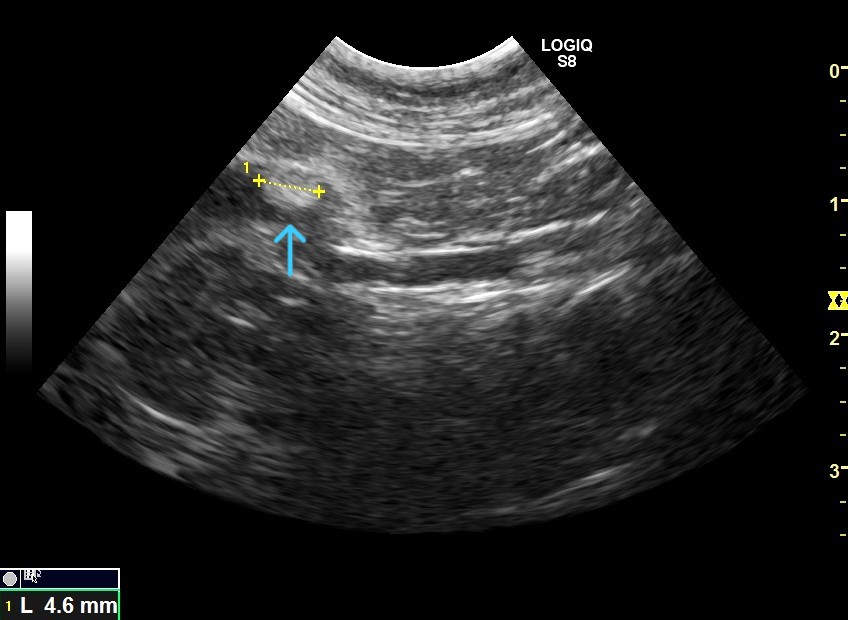

写真上矢印 胆嚢内に認められた多数の胆石